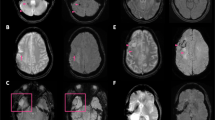

We observed that the 3D data from this “auto-align” sequence approached diagnostic quality, with reasonable T1-weighting and excellent conspicuity of gadolinium-based contrast material. This observation motivated our development and clinical implementation of a modified version of the auto-align 3D-FLASH pulse sequence that provides diagnostic quality, volumetric T1-weighted whole brain imaging (Fig. 1) in about 1 min.

Normal contrast-enhanced 3D-FLASH images (a–c) and 3D-MPRAGE images (d–f) in a 22-year-old female with migraines. Images are reformated in the (a, d) sagittal, (b, e) axial, and (c, f) coronal planes. Time of acquisition for the whole brain 3D-FLASH sequence was 49 s, and time of acquisition for the whole brain 3D-MPRAGE sequence was 4 min and 35 s

Figures 2, 3, and 4 display comparisons between contrast-enhanced 3D-FLASH and 3D-MPRAGE.

Comparison of contrast-enhanced 3D-MPRAGE and 3D-FLASH images in a 67-year-old male with colon cancer metastases. a 3D-MPRAGE and b 3D-FLASH images display brain metastases in the anterior right frontal lobe, left frontal lobe (two), and left thalamus. 3D-FLASH shows comparable diagnostic performance despite ~ 5-fold reduction in acquisition time relative to 3D-MPRAGE

Motion artifact and susceptibility artifact on 3D-MPRAGE versus 3D-FLASH. a, b 54-year-old male with melanoma metastases. a Contrast-enhanced 3D-MPRAGE sequence is degraded by motion artifact, obscuring a small left frontal lobe metastasis that was missed by both neuroradiology readers. b Contrast-enhanced 3D-FLASH sequence is less affected by motion artifact due to its faster acquisition time and more clearly displays the small left frontal lobe metastasis, which both readers detected on this sequence. c, d 14-year-old male with medulloblastoma and a ventricular shunt. The right occipital shunt valve causes local susceptibility artifact which is worse on c 3D-MPRAGE compared to d 3D-FLASH, owing to the longer time to echo and lower receiver bandwidth used for 3D-MPRAGE

Signal-to-noise ratio in 3D-MPRAGE versus 3D-FLASH. a, b 27-year-old female with multiple sclerosis. An enhancing demyelinating plaque is present in the posterior left frontal lobe white matter (arrows). Both neuroradiologist readers detected the enhancing plaque on the a 3D-MPRAGE sequence where it was more conspicuous. Neither reader detected the lesion on the b 3D-FLASH sequence. The 1-min 3D-FLASH images have lower signal-to-noise ratio than the 4.5-min 3D-MPRAGE images, which might reduce the detectability of very small or mildly enhancing lesions